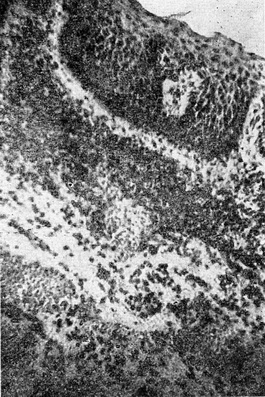

Мікроскопічно (біопсія до лікування): дифузні інфільтрати в підслизовому шарі з круглих, плазматичних клітин та поодиноких лейкоцитів. Значне потовщення і метаплазія покривного епітелію в багатошаровий плоский (рис. 7).

Рис. 7. Хронічний трихомонадний уретрит. Потовщення і метаплазія покривного епітелію в багатошаровий плоский. Інфільтрати в підслизовому шарі з круглих плазматичних клітин та поодиноких лейкоцитів.